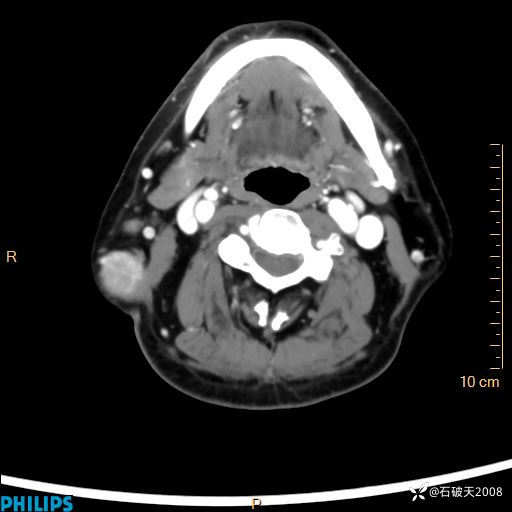

病例分享:颈部占位,一周后公布病理

男 57岁 主 诉:发现右侧颌下肿物1月余。

现病史:1月余前家属发现右侧颌下肿物。局部皮肤无红肿、热痛,无吞咽困难,无异物感,无恶心、呕吐,无头痛、头晕,无胸闷、胸痛,无发热、咳嗽、咳痰及呼吸困难。于我院行体表肿块彩超检查(2024.03.15我院)示:右侧耳下皮下软组织内低回声,未治疗。今为进一步治疗门诊以“腮腺肿瘤”为诊断收住我科,发病来患者神志清,精神可,饮食、睡眠及大小便正常,体重无明显下降。

MIP